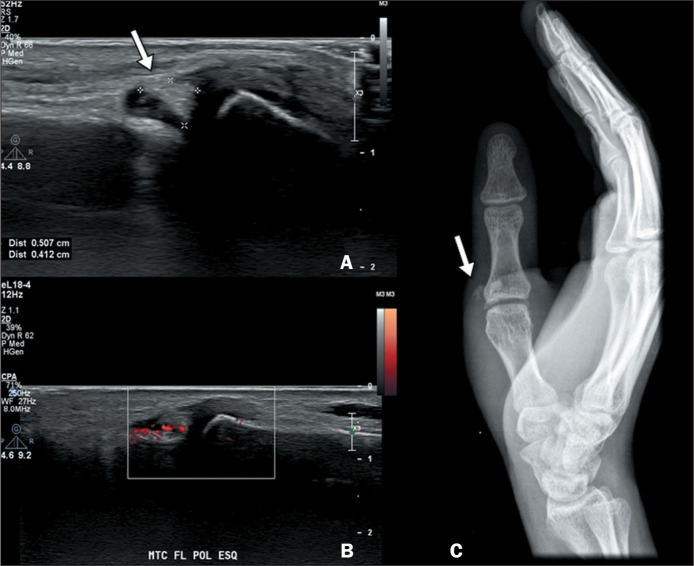

急性钙化性关节周围炎(ACP)是指与羟基磷灰石和其他碱性磷酸钙晶体在关节内沉积有关的关节周围炎。ACP 患者会突然出现疼痛、局部肿胀、红斑、压痛和活动范围减小。熟悉 ACP 的临床和影像学表现有助于诊断,并有助于将其与其他疾病(尤其是感染性或炎症性病变,如化脓性关节炎和痛风)区分开来,从而减少不必要的诊断和治疗过程。这篇图文并茂的文章旨在说明 ACP 在不同关节中的成像结果,重点是磁共振成像的结果。

Acute calcific periarthritis (ACP) is defined as periarticular inflammation associated with intra-articular deposits of hydroxyapatite and other basic calcium phosphate crystals. Patients with ACP present with a sudden onset of pain, together with localized swelling, as well as erythema, tenderness, and reduced range of motion. Familiarity with the clinical and radiological manifestations of ACP aids in the diagnosis and helps differentiate it from other conditions, particularly infectious or inflammatory pathologies such as septic arthritis and gout, thereby reducing the number of unnecessary diagnostic and therapeutic procedures. The objective of this pictorial essay is to illustrate the imaging findings of ACP in various joints, with an emphasis on the findings obtained by magnetic resonance imaging.